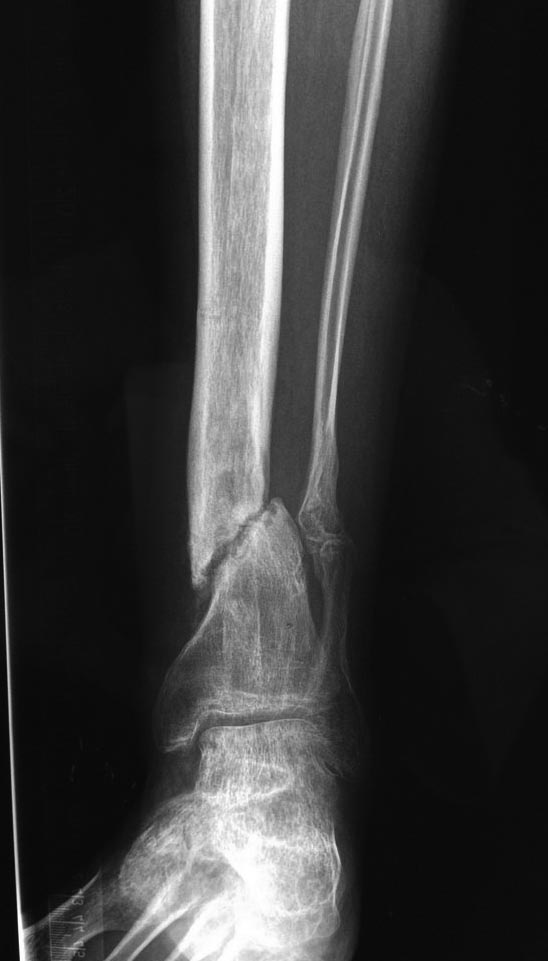

Уважаемые коллеги выразите Ваше мнение по следующему случаю.Молодой человек, 27 лет, находится на лечении с диагнозом: Ложный сустав большеберцовой кости в нижней трети, фиксированный интрамедуллярным блокированным стержнем (12.02.2014 г), ложный сустав малоберцовой кости в нижней трети левой голени, посттравматический артроз левого голеностопного сустава 1 стадии. Укорочение левой нижней конечности на 1,0 см. Со слов пациента известно, что в детстве получил перелом большеберцовой кости, лечился консервативно, перелом сросся с деформацией. Травма в июле 2010 г. бытовая-упал на лестнице, получил перелом малоберцовой кости, и перелом большеберцовой кости без смещения. Выполнена операция: Остеотомия большеберцовой кости в нижней трети, интрамедуллярный блокированный остеосинтез большеберцовой кости левой голени. Гладкое течение послеоперационного периода. Перелом большеберцовой кости сросся. Функция конечности восстановилась. В июне 2013 г выполнена операция удаление интрамедуллярного стержня из большеберцовой кости левой голени. Гладкое течение послеоперационного периода. Приступил к занятием физкультурой, бег. В августе 2013 г спрыгнул с автобуса, с чемоданом в руках, появилась резкая боль в левой голени. За медицинской помощью обратился через 7 дней, при обследовании выявлено: Рефрактура большеберцовой кости. Рекомендовано консервативное лечение в гипсовой повязке. В январе 2014 г. установлен диагноз: Ложный сустав большеберцовой кости в нижней трети, малоберцовой кости в нижней трети левой голени. Контрактура сгибательно - разгибательная левого голеностопного сустава. Посттравматический артроз левого голеностопного сустава 1 стадии. Укорочение левой нижней конечности на 1,0 см. В феврале 2014 г выполнил первым этапом: Фиксацию ложного сустава в АНФ с восстановлением осей сегментов. Через семь дней БИОС с рассверливанием. После операции - вальгус голеностопного сустава. Гладкое течение послеоперационного периода. Нагрузка по переносимости боли. Через 6 недель динамизация, через 2 недели стали мигрировать 2 фронтальных винта. Пытался подкрутить, пришлось удалить. Через 6 мес., контроль - линия ложного сустава прослеживается, но имеется периостальная костная мозоль. Не хватает стабильности.Вопрос что делать?Вариант № 1- выполнить реостеосинтез с рассверливанием КМК и на 12 мм диаметра гвоздь (стоит 11 мм)и убрать ротацию стопы руками одномоментно или одномоментно при помощи АНФ во время операции. Вариант № 2 выполнить удаление гвоздя, сделать все то же, что 6 месяцев назад, но с восстановлением анатомических взаимоотношений в голеностопном суставе.Вариант № 3 Двухэтапно, вторым этапом пластина на большеберцовую кость + костная пластика области не сращения.Вариант № 4 удаление гвоздя и лечение в КДА. Вопросы:1. Какой вариант оперативного лечения будет оптимальным в данном случае.2. При двухэтапной методике в дистальном отломке имеется канал от гвоздя, как направить гвоздь к наружному отделу дистального отломка большеберцовой кости. Есть опасения, что гвоздик может пойти по тому же каналу. Использовать поллер спицы или винты – сработают ли? И достаточна ли будет жесткость фиксации дистального отломка большеберцовой кости на гвоздике при 3 – 4 винтах при реостеосинтезе гвоздем.3. Нужен ли остеосинтез малоберцовой кости в нижней трети, с целью создания латеральной опоры. К сообществу за советом.

Тут не очень понятно, какой снимок самый недавний. Лучше бы их отправлять не указанием срока или еще чего-то в названии, а просто с порядковой нумерацией.